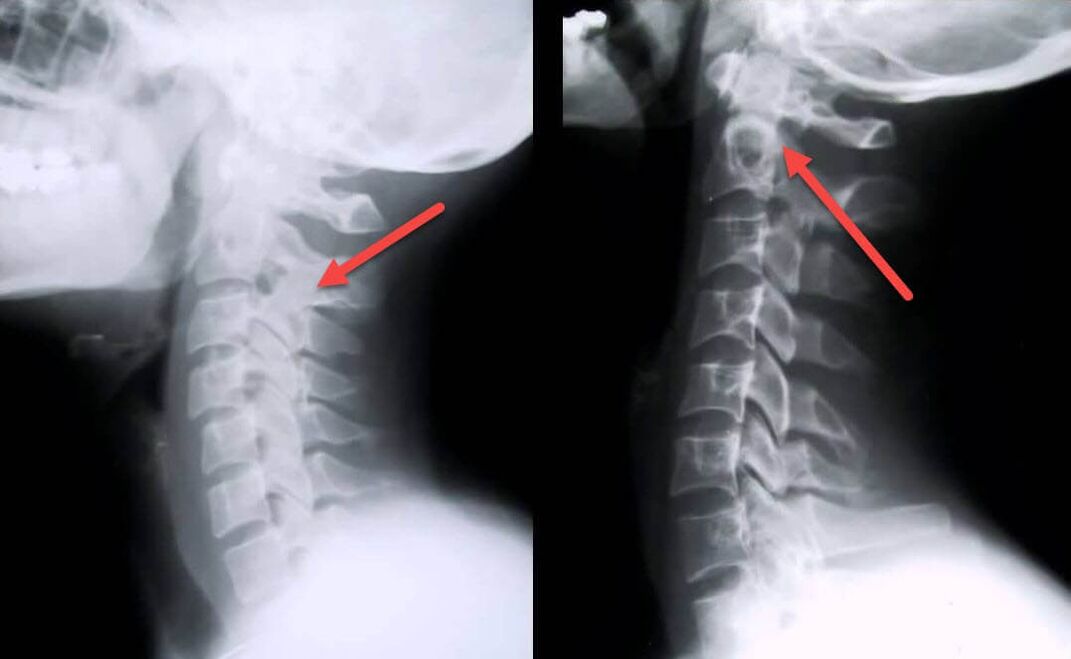

Najbolj informativen diagnostični postopek je radiografija. Patologije 1. stopnje ustrezajo 1. ali 2. radiološki stopnji. Nastale slike prikazujejo značilne znake bolezni.

| Rentgenske stopnje cervikalne osteohondroze 1. stopnje | Značilni znaki |

|---|---|

| 1. stopnja | Manjše spremembe v ukrivljenosti hrbtenice v vratnem predelu, ki prizadene enega ali več segmentov |

| 2. stopnja | Rahla zadebelitev medvretenčnih ploščic, deformacija uncinatnih izrastkov, izravnava lordoze, manjše rasti kostnih struktur. |